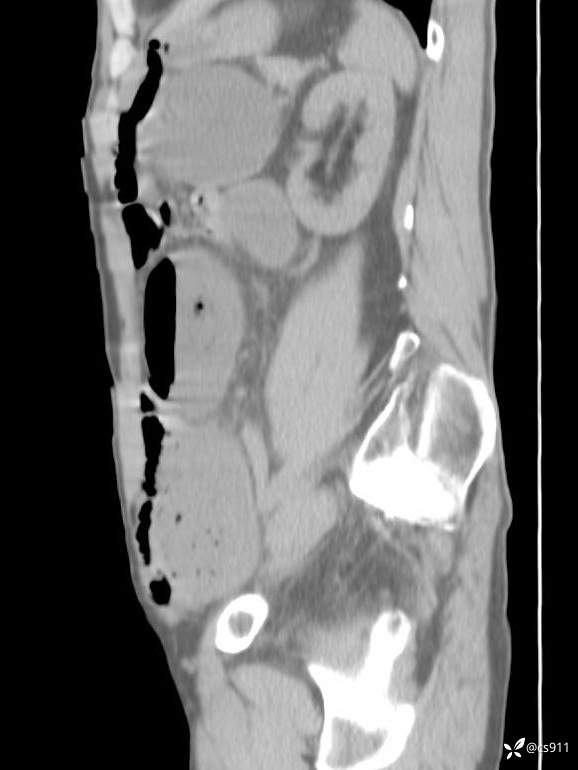

急腹症之急诊CT,原因?答案公布

男,77岁,腹痛、腹胀伴恶心呕吐1天。呕吐胃内容物,非喷射性呕吐,有咖啡色样胃内容物,诉有胃穿孔病史。查体:全腹平,下腹部压痛,全腹无反跳痛,叩诊呈浊音,移动性浊音阴性,肠鸣音减弱,1-2次/分。肛检:直肠未扪及明显肿物,可触及大量粪块。

T 36.6℃ P 80次/分 R 26次/分 BP 100/60mmHg

白细胞(WBC) H 14.55 10e9/L 4-10

红细胞(RBC) 4.58 10e12/L 4.3-5.8

中性粒细胞百分率(NEUT%) H 85.7 % 40-75

血淀粉酶(AMY) HH 1859 U/L 35-135

癌胚抗原(CEA) H 27.44 ng/ml 0-5

呕吐物 潜血试验 * 阳性 阴性

患者轮椅入室检查神志清楚, 能配合摆位和呼吸